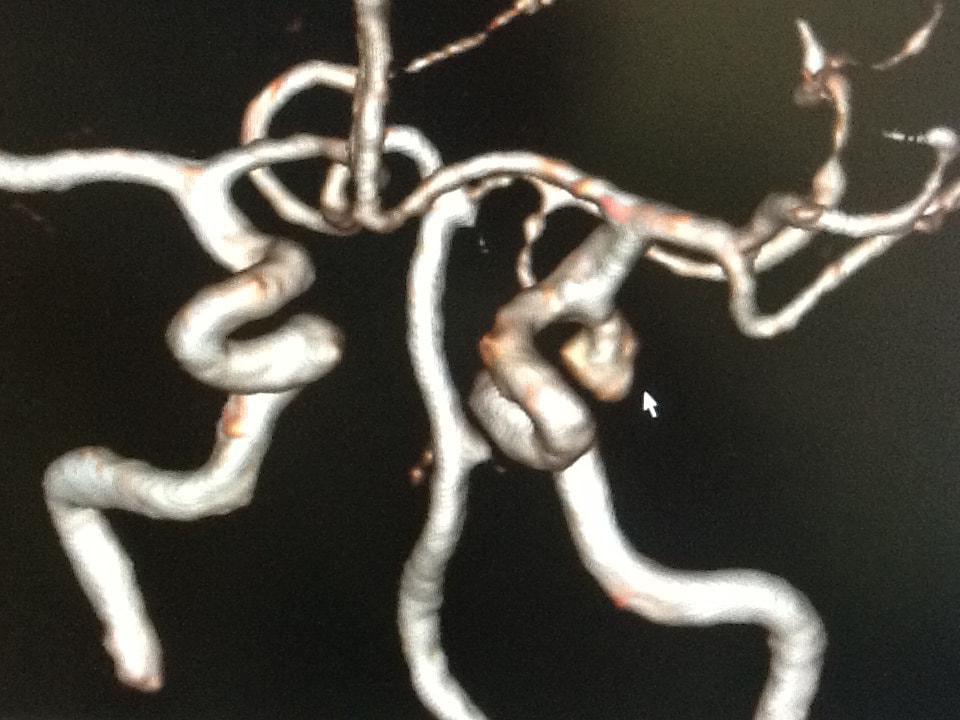

当院は神経系の専門クリニックです。頭痛やめまい、顔のしびれや痛み、てんかんやけいれん、肩こりや腰痛、手足のしびれや震え、物忘れや記憶障害や意識障害、頭部打撲など、気になる症状がございましたら、何なりとお申し出下さい。

MRIドックのご案内

当クリニックでは脳神経外科領域の診療の他にMRIを用いた様々な検診メニューをご用意いたしました。『病状はなく病院へ行くほどではないけれど何か気になる』『ご自身の体の状態を正確に知りたい』などの場合にお役に立てる事と存じます。

病気の早期発見のために、最新のMRIを用いた本格的な検診。

大病院などで用いられている最新のMRIを使用し、精度の高い結果を得、かつ痛みや不快感を極力排除することを可能にしました。

検査画像は、豊富な経験を持つ専門性の高い読影医が担当し、読みやすく質の高いレポートとしてご提供します。また、ご要望に応じて、医師の説明を受けながら、自分の目で検査の画像を確認し、現在の健康の状態を理解して頂くことも出来ます。